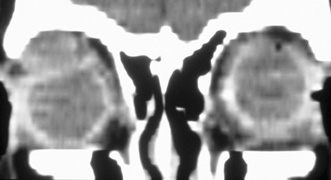

Fig. 6. Lateral orbitotomy through upper eyelid skin crease A. Photo demonstrating right globe ptosis present for more than 2 years. B. Axial CT scan showing a well outlined oval lesion in the lacrimal gland

fossa. C. Coronal CT showing lesion pushing globe inferiorly. D. Skin crease excision marked for lateral orbitotomy. E. Lateral orbital rim exposed. Bone cuts made above frontozygomatic suture